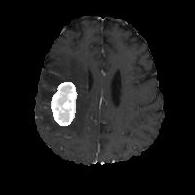

(a) (b) (c) (d)

Boundary Stream:

Fig. 2 demonstrates the output of each of the attention layers in our dedicated boundary stream. In essence, each attention layer progressively localizes the tumor and refines the boundaries. The first attention layer has learned rough estimate of the boundaries around the tumor and localized it, whereas the second and third layers have learned more fine-grained details of the edges and boundaries, refining the localization. Moreover, since our architecture leverages a dilated spatial pyramid pooling to merge the learned feature maps of the regular segmentation stream and the boundary stream, multiscale regional and boundary information have been preserved and fused properly, which has enabled our network to capture the small structural details of the tumor.

(a) (b) (c) (d) (e)